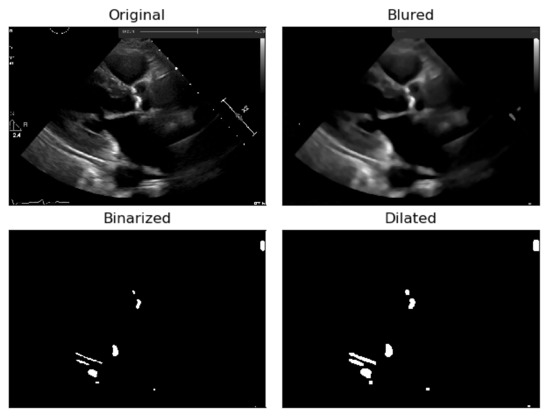

To deal with some natural constraints in terms of noise that characterize echocardiography imaging, particularly the process of sampling still images from the echocardiography video, different blurring treatments were performed to clean some of the image’s noise due to the echocardiography’s motion. Blurring an image will average rapid changes in the different pixel intensities, and this corresponds to a low-pass filter applied to the image [23], which removes noise while leaving the majority of the image structures still present in the image as depicted in Figure 4.

As it can be seen from Figure 4, when the Blur = 11 (experimentally adjusted with trial and error)), it can be easily identified, visually, in the regions where there is a presence of calcium (identified by the red circles). On this operation the central element of the image is replaced by the median of all the pixels in the kernel region, where the 11 means that it takes into consideration a kernel of 11 by 11.

In Figure 5, it is noticeable that when the blurring parameter increases from 5 to 11, we get a cleaner image (without small white dots—noise). However, we can also notice that in the region of interest (marked with red circles), when the blur increases, we lose pixels, since the region gets smaller. To mitigate this, a mask dilation operator was applied to each region of interest.

Figure 4. Echocardiography image with four levels of blurring applied—the red circle represents our ROI where the aortic valve is located.